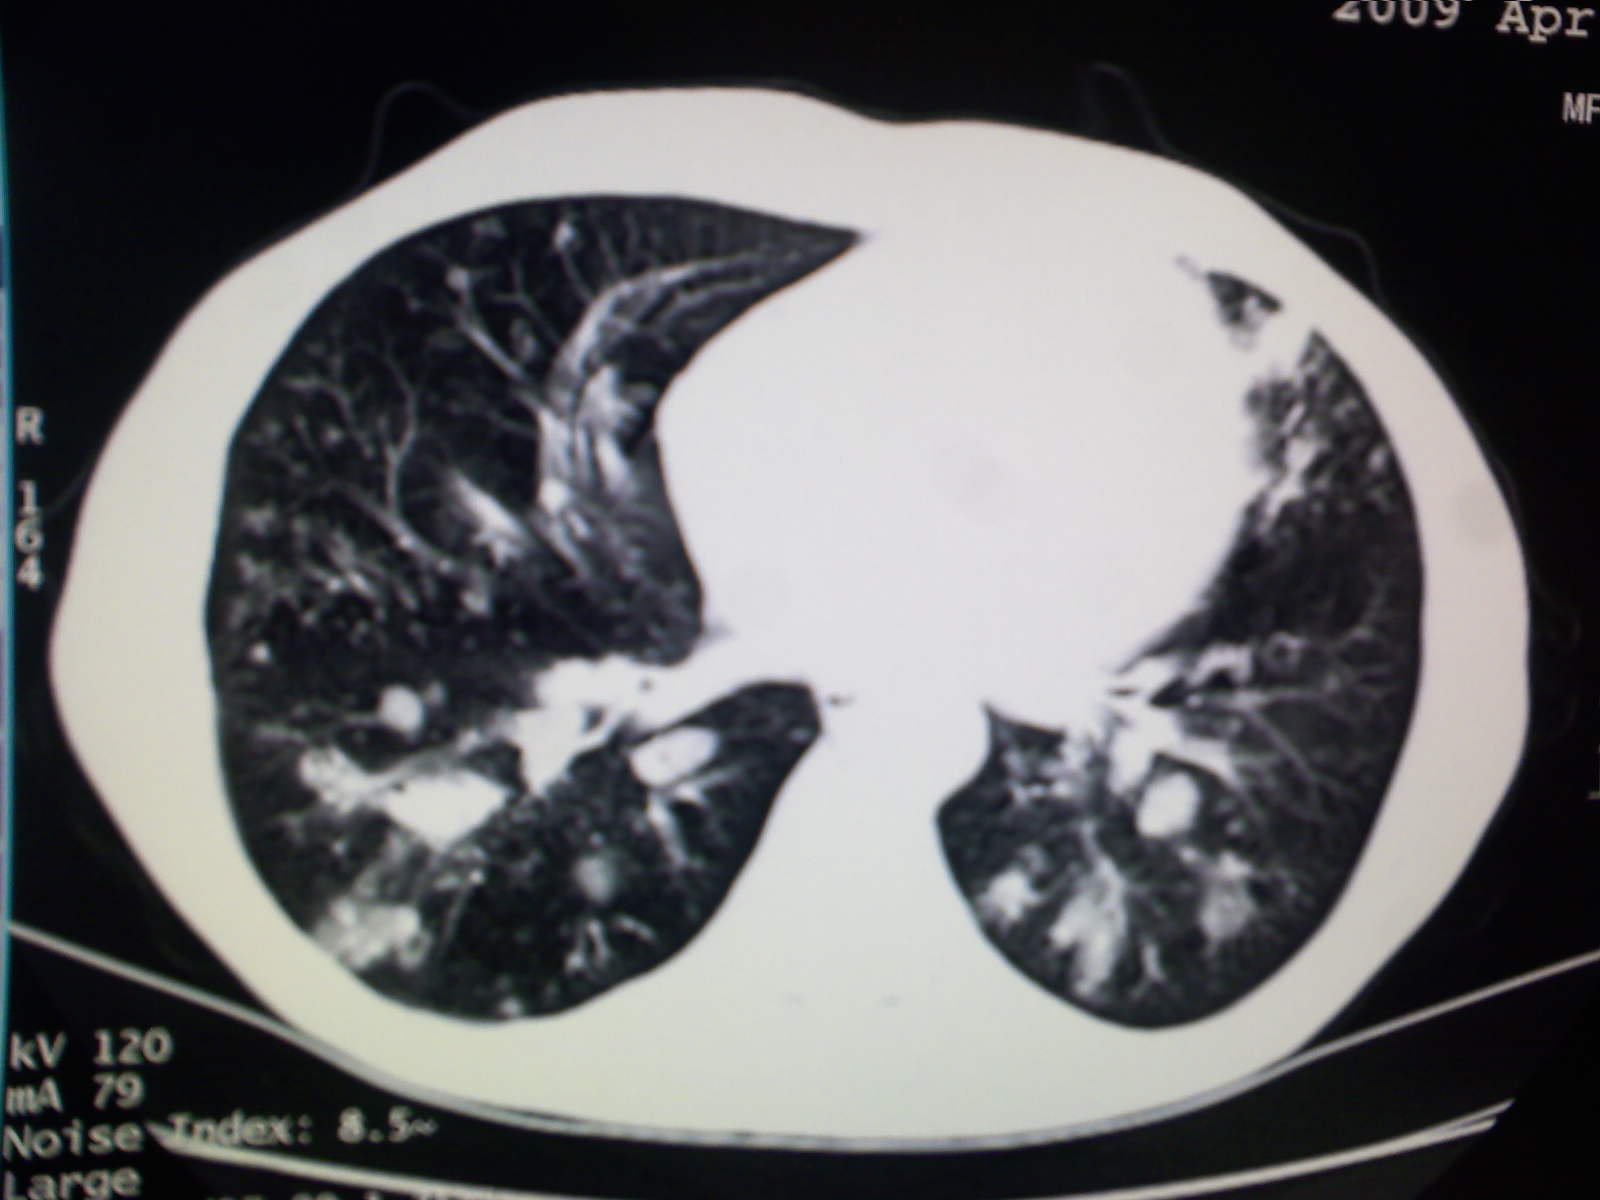

以下是引用卜一在2009-4-11 15:50:00的发言:[br]双肺继发性肺结核伴空洞形成,不排除合并霉菌感染!(病灶呈多形态 多特征 散在分布)。另:合并支气管扩张征伴感染!

以下是引用主力军在2009-4-11 15:55:00的发言:[br]两肺继发性肺结核可能性大。

以下是引用康鹏在2009-4-11 16:30:00的发言:[br]双肺继发性肺结核伴空洞形成合并感染[br]支气管扩张合并感染